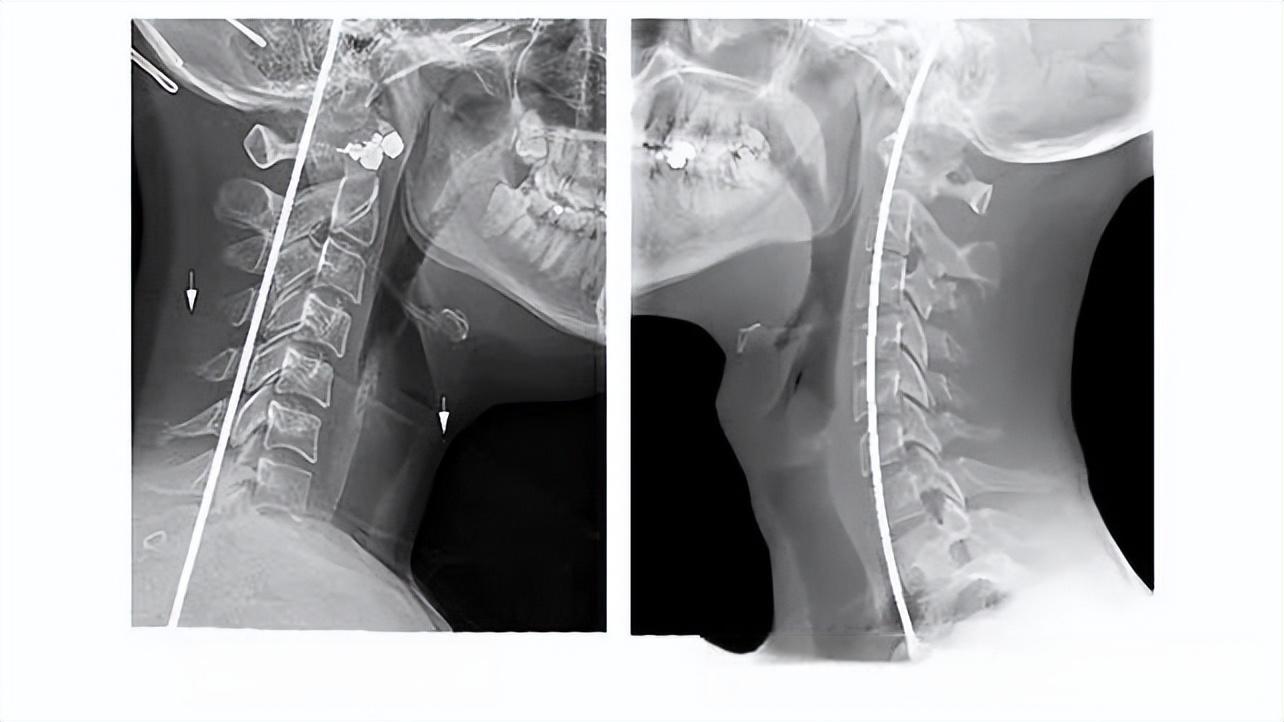

颈椎X线片是诊断颈椎疾病的重要工具之一。通过X射线穿透人体组织并记录影像,医生可以观察颈椎的形态、结构、椎间隙和椎间孔等变化,从而判断颈椎病的类型和程度。

在颈椎病诊断中,常用的X线摄影技术包括颈椎正位片、侧位片、斜位片以及开口位片等。正位片用于观察颈椎的排列顺序、椎体骨质的完整性;侧位片评估颈椎的生理曲度、椎间隙的高度;斜位片和开口位片则有助于揭示颈椎是否存在钩椎关节骨质增生或齿状突骨折等问题。

颈椎X线片能提供丰富的诊断信息。例如,它可以显示颈椎曲度是否异常,正常颈椎的生理曲度呈前凸状,如果曲度消失、变直或反张,可能提示颈椎稳定性受到破坏。此外,X线片还能显示椎体边缘是否有骨质增生,这是随着年龄增长和颈椎间盘退变而出现的常见现象。骨质增生在X线片上表现为沿着椎体边缘的唇样突起,严重时可以呈骨桥样改变。

椎间盘变性和突出也是X线片能观察到的重要信息。椎间盘退变时,椎间隙会变窄,前窄后宽或前后等宽。当椎间盘发生突出时,在侧位X线片上表现为“双边征”,即椎间隙后缘出现双边现象。此外,X线片还能显示颈椎管是否狭窄,以及神经根是否受压。